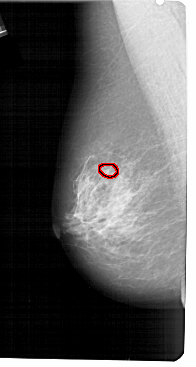

A_1706_1.LEFT_MLO

LEFT_MLO LINES 5491 PIXELS_PER_LINE 2926 BITS_PER_PIXEL 12 RESOLUTION 43.5 OVERLAY

FILE: A_1706_1.LEFT_MLO.OVERLAY

TOTAL_ABNORMALITIES 1

ABNORMALITY 1

LESION_TYPE CALCIFICATION TYPE PLEOMORPHIC DISTRIBUTION CLUSTERED

ASSESSMENT 4

SUBTLETY 1

PATHOLOGY BENIGN

TOTAL_OUTLINES 1

BOUNDARY